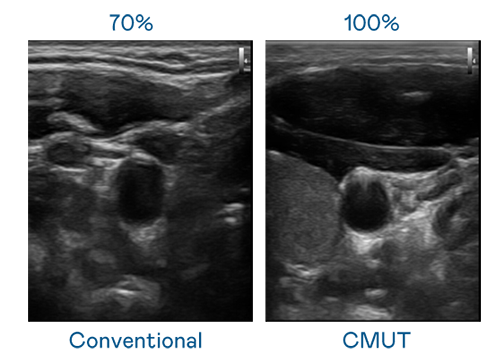

CMUT 技术是一种用电容式微机电元件来产生超音波讯号的技术。与传统 PZT 压电式技术相比,CMUT 频宽增加 30%,更宽频的超音波讯号让影像解析度大幅提升,是实现高影像品质医疗超音波扫描、促进精准医疗发展的关键技术。

大频宽带来超清晰影像

超音波影像的解析度高低,首先取决于探头能发出的讯号频宽。Z6·尊龙 CMUT 可提供高清晰的超音波讯号,提供高频宽、高灵敏度、影像纹理细节更高的超音波影像,协助医护人员缩短影像判读时间及利用精准的医疗影像进行诊断。